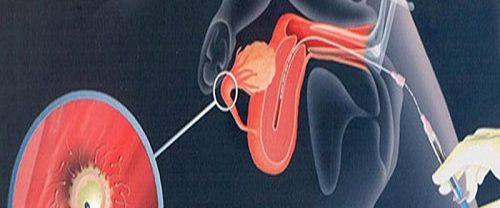

Yapay İnseminasyon Aşılama Kavramı ve Tanımı: Yapay İnseminasyon Aşılama, tıbbi bir prosedürdür ve çiftlere gebelik şansını artırmak için kullanılan bir yöntemdir. Yapay inseminasyon, spermlerin kadının üreme sistemine yerleştirilmesini içerir. Bu prosedür, sperm hücrelerinin kadının rahmine ulaşmasını kolaylaştırarak döllenme şansını artırır. Yapay inseminasyon, çeşitli durumlarda kullanılabilir. Bunlar arasında sperm kalitesinde sorunlar, düşük sperm sayısı, hareketlilik sorunları,…

Vakumlu Aspirasyon Yöntemi İle Kürtaj Vakumlu Aspirasyon Yöntemi İle Kürtaj, istenmeyen gebeliğin sonlandırılması amacıyla yapılan tıbbi bir prosedürdür. Bu prosedür, gebelik dokusunun rahimden çıkarılması işlemidir. Vakumlu aspirasyon yöntemi, günümüzde yaygın olarak kullanılan modern bir kürtaj tekniğidir. Bu yöntem, etkili, güvenli ve hızlı bir şekilde gebeliğin sonlandırılmasını sağlar. Vakumlu Aspirasyon Yöntemi İle Kürtaj yöntemi, uterus içerisindeki…

OPU Sperm Ovum ve Embriyo Prezervasyon OPU Nedir? OPU Sperm Ovum ve Embriyo Prezervasyonu | OPU, yani “Oosit Pick-Up” veya “Yumurta Toplama”, tüp bebek tedavisinde önemli bir adımdır. Bu prosedür, overlerde olgunlaşan yumurtaların (ovumların) cerrahi olarak toplanması işlemidir. Genellikle tüp bebek tedavisinin belirli bir aşamasında gerçekleştirilir ve tedavinin başarısı için kritik bir rol oynar. OPU,…

IVF İn Vitro Fertilizasyonun Temel İlkesi IVF İn Vitro Fertilizasyon, doğal olarak gebe kalamayan çiftlere yardımcı üreme teknikleri arasında en yaygın kullanılan yöntemlerden biridir. Temel ilkesi, gametlerin (yumurta ve sperm) laboratuvar ortamında bir araya getirilerek döllenmelerinin sağlanması ve oluşan embriyoların rahim içine transfer edilerek gebelik elde edilmesidir. İn vitro fertilizasyon süreci, bir dizi aşamadan oluşur:…